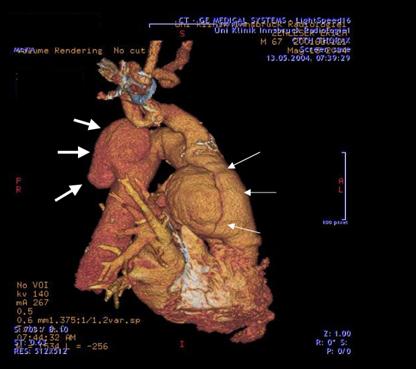

Schließlich sollte der Vollständigkeit halber auch erwähnt werden, dass in den letzten Jahren zunehmend endovaskuläre, interventionelle Verfahren Eingang in die thorakale Aortenchirurgie gefunden haben, d.h. Prothesen können zur Stabilisierung von Aneurysmen (meist) über die Leistengefäße eingebracht werden und im Bereich der (sackartig) erweiterten Hauptschlagader positioniert und expandiert werden. Sie stabilisieren somit die Schwachstelle, exkludieren die sackartige Erweiterung der Schlagader und reduzieren das Rupturrisiko. Dies kann in einigen Fällen dem Patienten eine aufwändige Operation mit Eröffnung des Brustkorbes ersparen (Abb. 3a. und 3b.). Die Entwicklung dieser implantierbaren Prothesen (Stents) läuft derzeit so stürmisch ab, dass noch nicht absehbar ist, welche Bereiche der Aortenchirurgie und in welchem Ausmaß zukünftig interventionelle Verfahren die etablierte herzchirurgische Aortenchirurgie ersetzen werden.

Abb. 3a. Aneursma der Aorta ascendens (dünne Pfeile) uns nierenförmiges Aneurysma der Aorta descendens (dicke Pfeile)